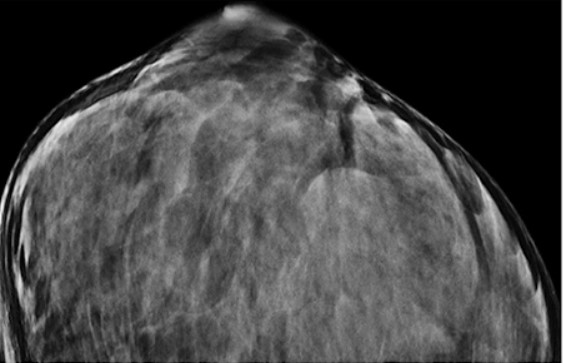

Ultrasound appearance of dense breasts.Fig.1 Ultrasound appearance of dense breasts. (Lee SH, et al., 2022)

1. Lee SH, Moon WK. Glandular Tissue Component on Breast Ultrasound in Dense Breasts: A New Imaging Biomarker for Breast Cancer Risk. Korean J Radiol. 2022 Jun;23(6):574-580.